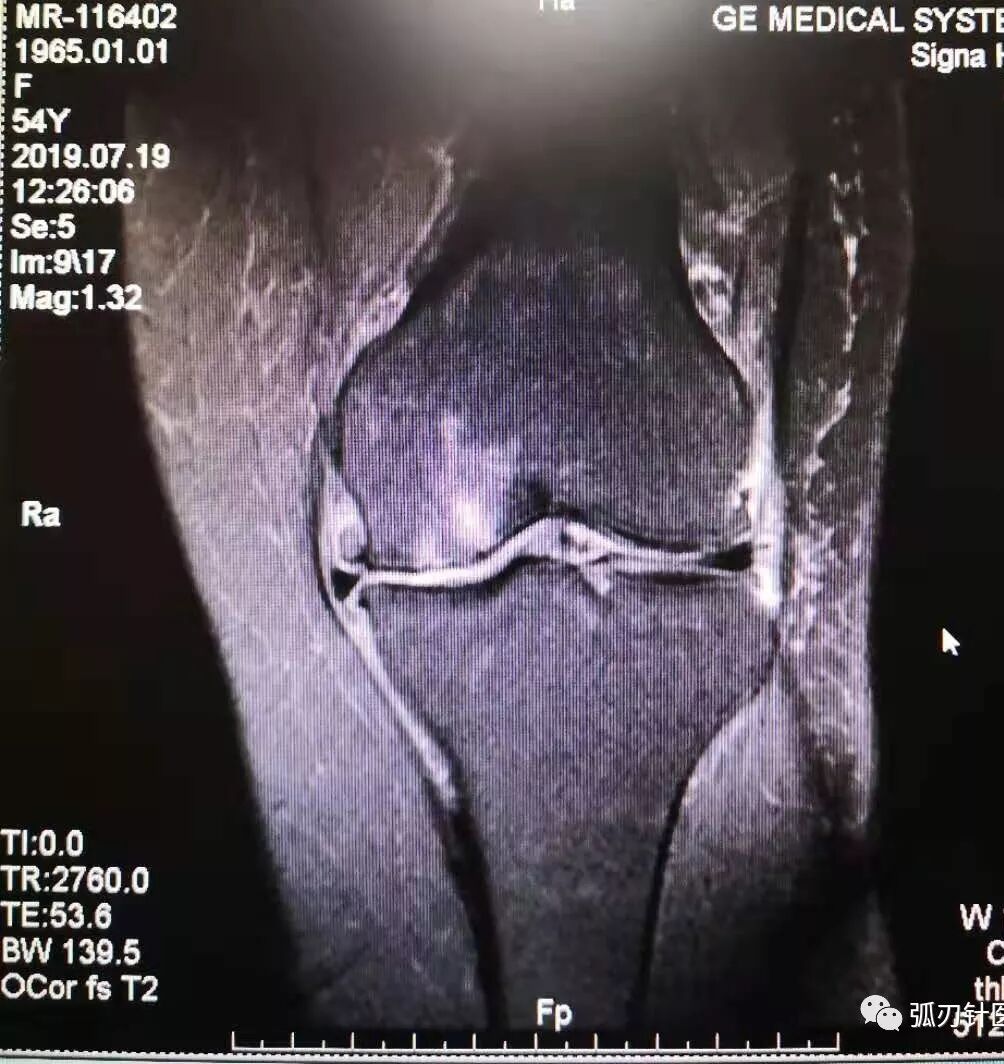

膝关节骨关节炎的磁共振影像

一例弧刃针标准疗法治膝关节骨关节炎的典型病例